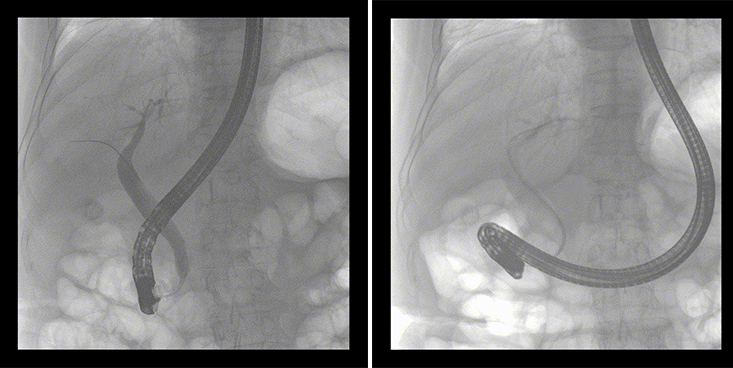

一位86歲的女性患者近來(lái)出現(xiàn)腹痛,入院后CT檢查并結(jié)合臨床表現(xiàn)被診斷為急性膽囊炎伴膽囊結(jié)石。經(jīng)專家團(tuán)隊(duì)協(xié)商并與患者家屬溝通,決定對(duì)患者實(shí)施經(jīng)內(nèi)窺鏡逆行胰膽管造影(ERCP)。

ERCP(經(jīng)十二指腸鏡下逆行胰膽管造影)現(xiàn)已成為比較成熟的微創(chuàng)介入技術(shù),被廣泛的應(yīng)用于臨床,ERCP也是消化內(nèi)鏡領(lǐng)域難度大、風(fēng)險(xiǎn)大、技術(shù)復(fù)雜的微創(chuàng)手術(shù),其并發(fā)癥多為致命性,ERCP手術(shù)對(duì)醫(yī)生的要求很高,因此,ERCP醫(yī)生又被稱為“刀尖上的舞者”。因?yàn)槭中g(shù)難度較大,過(guò)程復(fù)雜,需要C形臂精準(zhǔn)的配合,對(duì)影像清晰度的要求也非常高。

普愛(ài)醫(yī)療移動(dòng)式平板中C為本次ERCP手術(shù)提供實(shí)時(shí)無(wú)損高清影像,幫助醫(yī)生精準(zhǔn)定位?!俺上裥Ч浅0?!完全不輸國(guó)際大牌的醫(yī)學(xué)影像設(shè)備……”鼓樓醫(yī)院江北國(guó)際醫(yī)院內(nèi)鏡中心手術(shù)團(tuán)隊(duì)對(duì)普愛(ài)醫(yī)療移動(dòng)式平板中C的成像效果給與了高度的評(píng)價(jià)。

在消化內(nèi)科主任的領(lǐng)導(dǎo)和多科室全力配合下,南京鼓樓醫(yī)院江北國(guó)際醫(yī)院成功完成了首例ERCP手術(shù)。